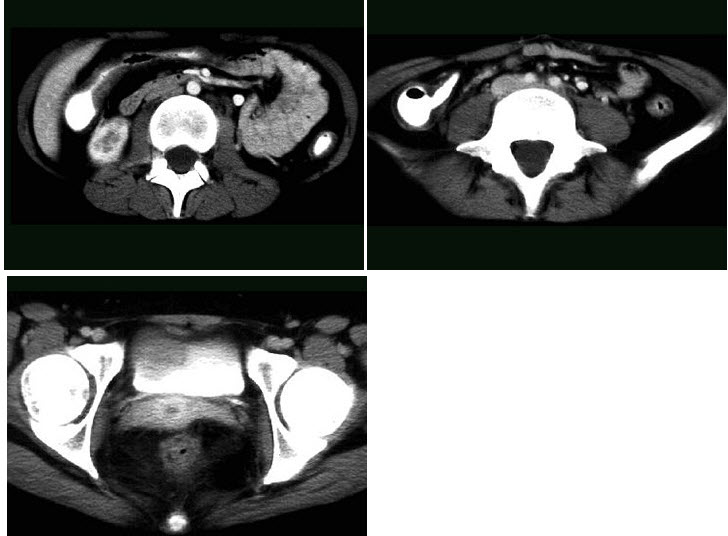

13、多项选择题

男,55岁,尿频,尿痛伴低热乏力1月。如图所示,下列说法正确的是()

A.左侧输尿管多发性狭窄

B.右侧肾积水

C.膀胱变形

D.左侧输尿管结核

E.左侧输尿管癌

点击查看答案

本题答案:微信扫下方二维码即可打包下载完整带答案解析版《★放射医学(医学高级)》或《放射医学(医学高级):CT》题库